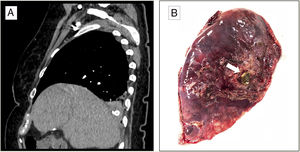

We report the case of a 73-year-old woman who presented in the emergency department of our hospital with suspected choking followed by a fit of coughing with bloody sputum. Her history was significant for complicated calculous cholecystitis 4 months previously, for which she underwent laparoscopic cholecystectomy. Her gallbladder was accidentally perforated during the surgical intervention, with spillage of gallstones to the peritoneal cavity. The initial exploration was normal, and no anomalies were detected in the analytical tests. The study was completed with a chest X-ray (normal) and a chest CT scan that revealed occupation of the right bronchial lumen and the presence of a foreign body with the density of calcium in the right lower lobe (RLL) (Fig. 1A). The patient was diagnosed with hemoptysis possibly associated with foreign body aspiration, so she was given prophylactic antibiotic therapy and a rigid bronchoscopy was performed. This technique revealed the presence of abundant blood clots and erythematous mucosa, with no foreign body in the airway. The clinical situation persisted, marked by recurrent episodes of hemoptysis. In view of this progress and the history of manipulation of the bile duct, we opted for a surgical approach to reach a definite diagnosis. RLL adhesions to the diaphragm were observed, so these were released, and an atypical resection was performed of the same lung lobe, corresponding to the site where the foreign body had been seen on the CT scan. After resection, the surgical specimen (12.5×6.5×3cm) was examined macroscopically and a gallstone was observed (Fig. 1B). The pathology study found organizing pneumonia on post-inflammatory bronchiectasis with an imbedded gallstone, along with fibrosis and chronic lymphohistiocytic inflammation with foreign-body giant-cell reaction. The postoperative period was uneventful, the patient was discharged to home, and the episodes of hemoptysis did not recur in the subsequent follow-up.